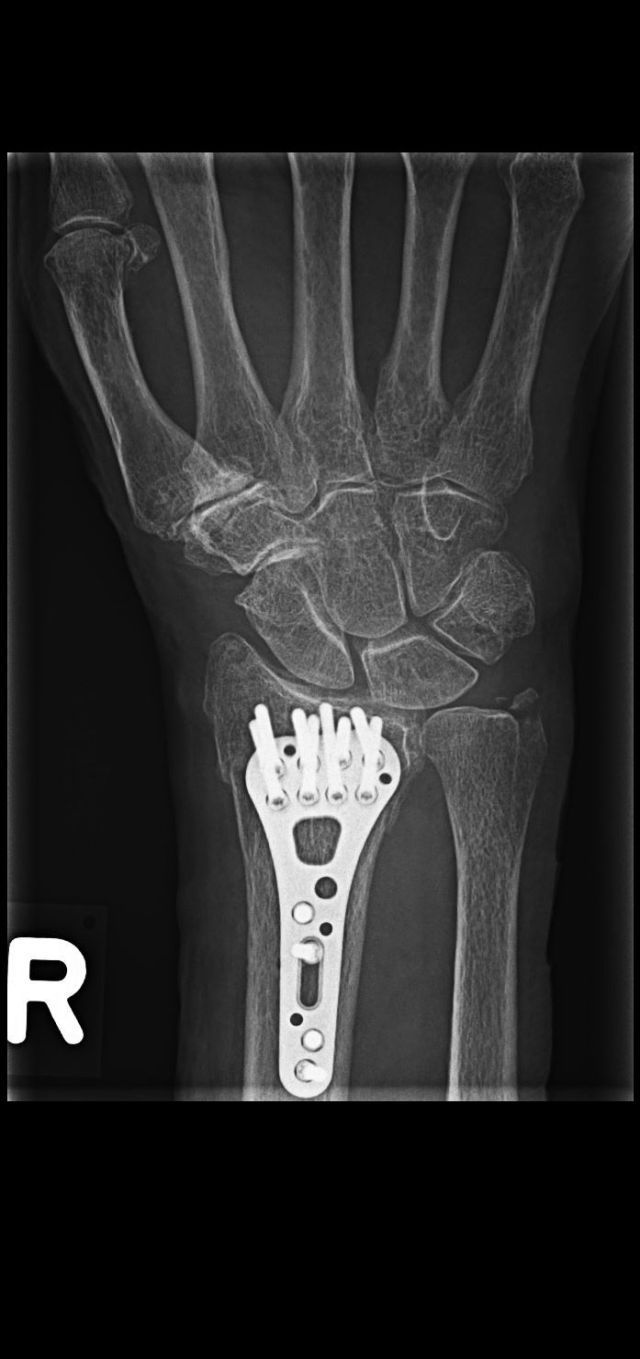

Röntgen des Skeletts und der Gelenke

Das Röntgen hat in der Orthopädie und Unfallchirurgie nach wie vor einen hohen Stellenwert. So können z.B. Knochenbrüche z.B. nach Unfall oder bei Osteoporose gefunden oder ausgekugelte Gelenke festgestellt werden. Ohne viel Zeit zu verlieren kann dann eine für Sie optimale Therapie begonnen werden. Auch das Ausmaß von Verschleißerscheinungen, die Arthrose, kann mit dem Röntgenbild festgestellt werden. In der Rheumatologie werden die Gelenke - meist Hände und Füße - geröngt, um das Ausmaß der entzündlichen Veränderungen am Knochen beurteilen zu können.

Osteoporose ist durch einen Verlust an Knochenmasse und eine Verschlechterung der Knochenqualität gekennzeichnet, bedingt durch ein Ungleichgewicht im Knochenstoffwechsel, bei dem der Knochenabbau überwiegt. Sie ist eine weit verbreitete Erkrankung vor allem von älteren Menschen. Eine der gravierendsten Folgen von Osteoporose sind Knochenbrüche, die aufgrund von minimaler oder sogar fehlender äußeren Belastung auftreten, sogenannte Insuffizienzfrakturen. Typische Orte für Insuffizienzfrakturen sind die Wirbelkörper der Wirbelsäule, das Handgelenk, der Oberschenkelhals und der Oberarm. Die Diagnose von Insuffizienzfrakturen erfolgt in der Regel zunächst durch Röntgenaufnahmen.